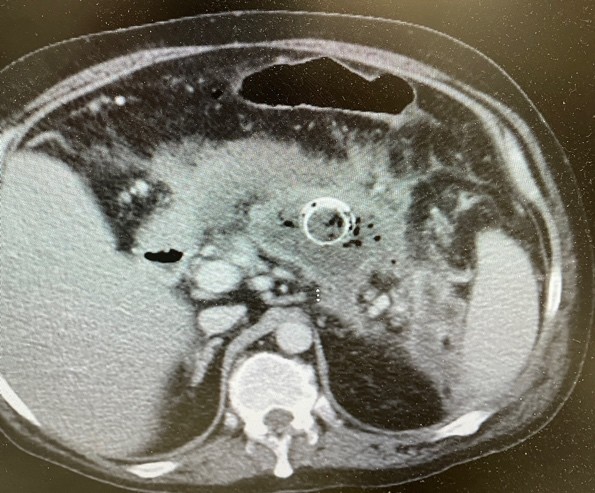

At the time of the initial EUS-guided drainage, the patient was only three weeks post-pancreatitis hospitalization. Due to the thin wall of the cavity, immediate necrosectomy was not performed since there was an increased risk of perforation. A week later he underwent necrosectomy. The procedure involved passing a double channel therapeutic scope into the esophagus and advanced into the stomach. EndoRotor powered endoscopic debridement catheter (Interscope), snare, and forceps were also used to remove the necroma from the cavity. The necrosectomy procedure had to be repeated three times due to the large size and mild bleeding to completely evacuate all the contents from the necrotic cavity. The repeat imaging showed complete healing and obliteration of the cavity and LAMS was successfully removed (Figure 2). There was a small left lower quadrant pelvic collection which could not be accessed by endoscopic ultrasound and was drained by the interventional radiologist. The drain was removed after complete resolution of the small collection. The patient returned to full time work and made a complete recovery without any sequela, such as kidney injury, lung injury or fistula formation.

Figure 2. Highlights the Lumen Apposing Stent (LAMS).

Figure 2